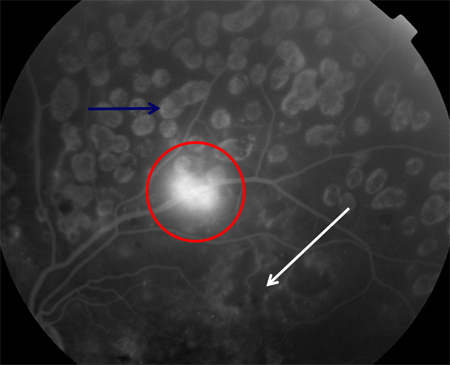

Fluorescein angiography in proliferative diabetic retinopathy: new vessels elsewhere (red circle), capillary non-perfusion (white arrow), pan-retinal laser burns (blue arrow)

Courtesy of Moorfields Photographic Archive; used with permission